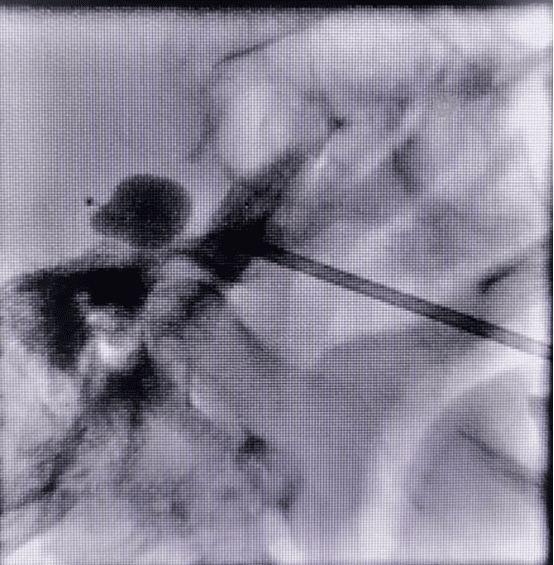

考虑到易奶奶高龄、基础疾病,邹聪建议患者选择在局麻下行微球囊压迫术。微球囊压迫术是一种高效治疗三叉神经痛的微创手术,整个创口仅一个针眼大小,操作时间约10分钟左右。在透视下确认穿刺方向和位置正确后,在半月神经节位置导入球囊导管,压迫三叉神经特定位置,从而使三叉神经痛觉纤维失活,达到治疗三叉神经痛的目的。该手术安全性高,术后疼痛立即缓解,恢复快,住院时间短。

(术中球囊形态)